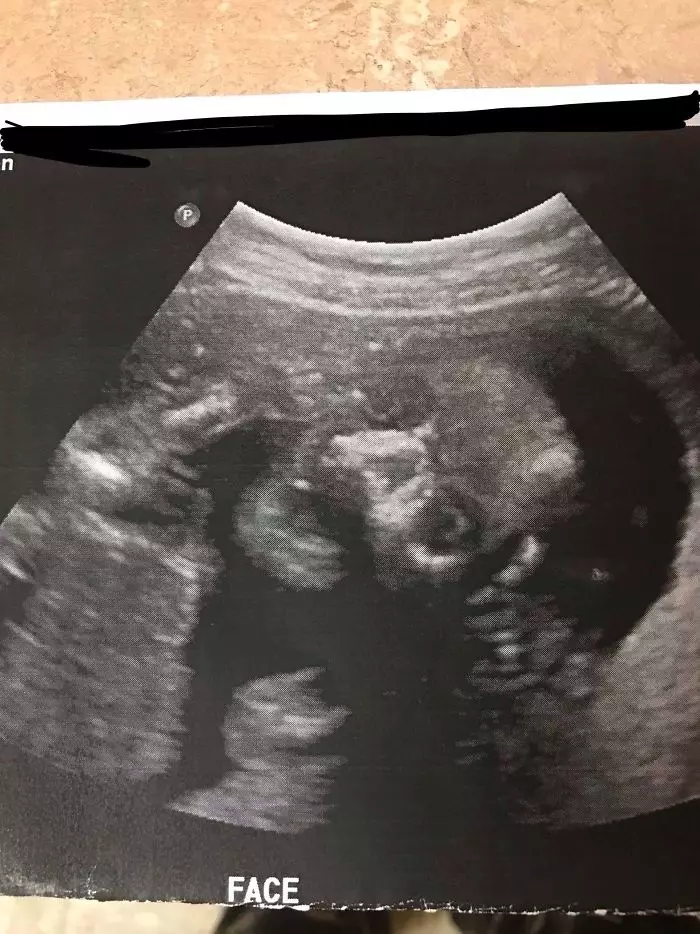

15. Foto USG bayi ini malah terlihat seperti tengkorak.